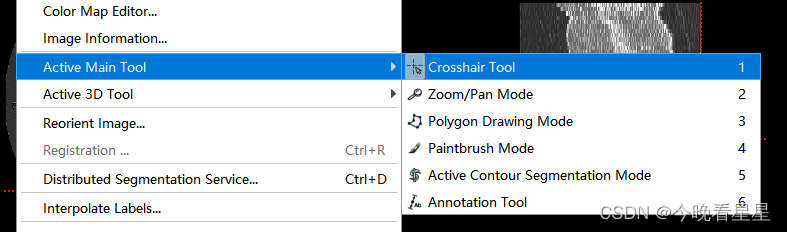

2.2 Active Main Tool

- 主要的标注工具

Crosshiar Tool即图像中的十字虚线定位点Zoom/Pan Mode用来缩放图像Polygon Drawing Mode多边形勾选区域,可以设定选定的模式,1)使用Smooth curve2) 使用Polygon多边形PaintBrush Mode用来涂画标注的区域Active Contour Segmentation Mode半自动进行区域的标注Annotation Tool可以标注图像上两点之间的距离,